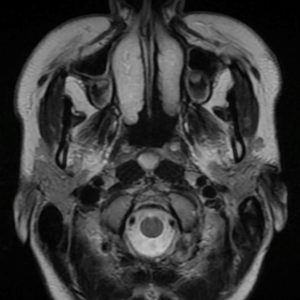

U dây VIII

Lượt xem: 140» 24-11-2018 -

U dây VIII

Lượt xem: 131» 24-11-2018 -

U dây VIII

Lượt xem: 143» 24-11-2018 -

U dây VIII

Lượt xem: 155» 24-11-2018 -